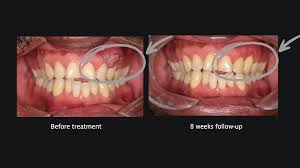

Cracked tooth syndrome, caused by injury or wear, can lead to intermittent or sharp pain, especially when chewing or exposed to hot or cold. At Rehan Dental Surgery, our specialists assess the type, location, and extent of the crack to provide precise treatment, aiming to save the tooth and restore long-term, pain-free function.

Before And After Treatment